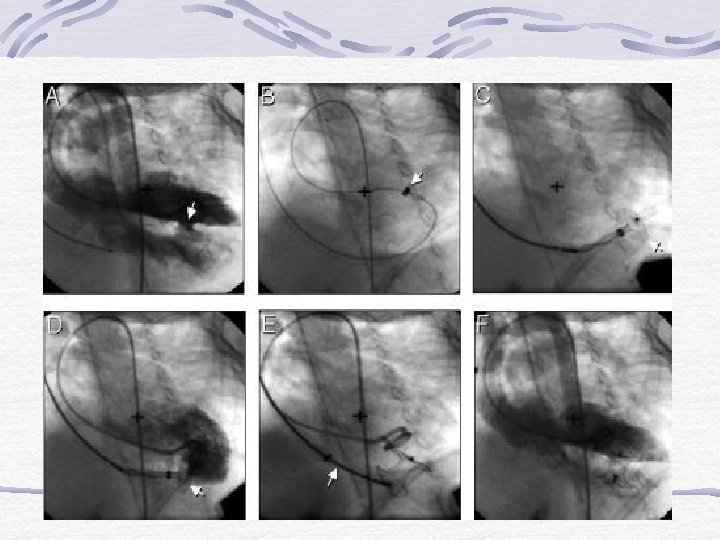

Transkateter VSD Kapatılması § Cerrahi blok § Ventrikülotomiye bağlı erken ve geç aritmiler § Postperikardiyotomi sendromu § Orta-büyük müsküler VSD’lerin cerrahi yöntemle kapatılması zordur. § Multipl VSD’lerde bu zorluk daha da belirgindir. § Miyokardiyal infarktüse bağlı VSD’lerin cerrahi mortalitesi yüksektir.

Amplatzer Müsküler VSD Cihazı § Değişik büyüklükte cihazlar vardır. § Küçük kılıflar aracılığı ile kullanılabilir. § Geri alınabilir, bu sırada deforme olmaz

Komplikasyonlar §AV kapaklarda hasar §Semiluner kapaklarda hasar §Ventriküler aritmi §Hipotansiyon §Giriş yerinde kanama §Tamponad §Ölüm